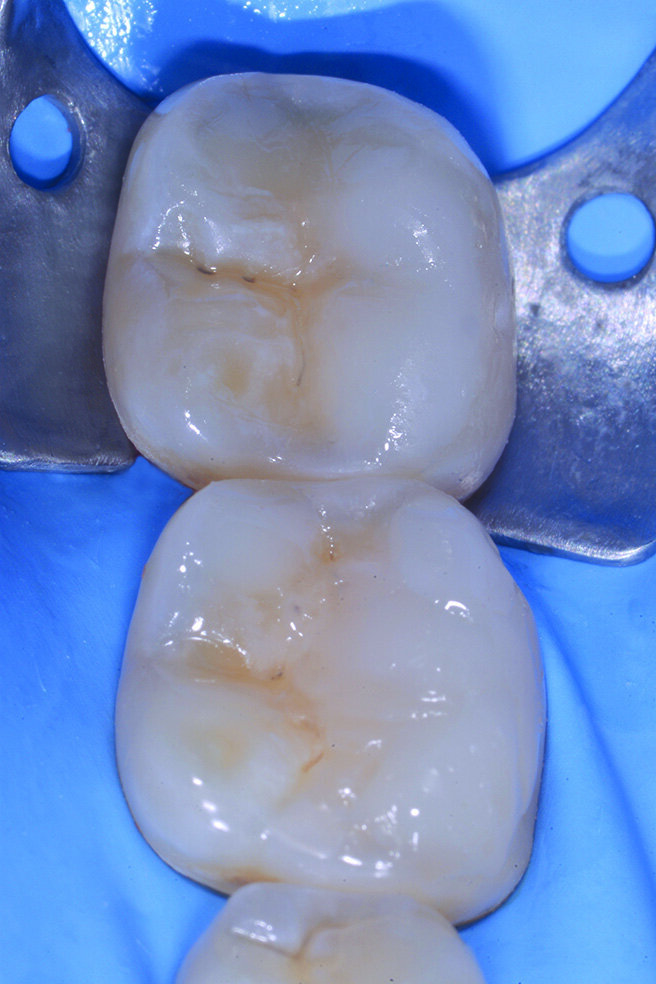

Figg. 2-5_Rimozione dei vecchi restauri presenti su 4.6 e 4.7: gli elementi vengono restaurati con tecnica diretta utilizzando dentina e smalto Enamel Plus HRI Bio Function.

Per evitare preparazioni che porterebbero al sacrificio di tessuto sano si preferisce ricostruire gli elementi in modo ultraconservativo con una tecnica diretta per addizione. I restauri presenti su 4.6 e 4.7 vengono rimossi e tutte le superfici da ricostruire sabbiate con ossido di alluminio e lo smalto interessato all’adesione viene poi lucidato con un gommino in silicone prima delle fasi adesive. Le cavità su 4.6 e 4.7 vengono prima riempite con piccoli incrementi di dentina quindi tutte le superfici occlusali erose e/o abrase vengono ricostruite con strati sottili di smalto composito (Enamel Plus HRi Bio Function).